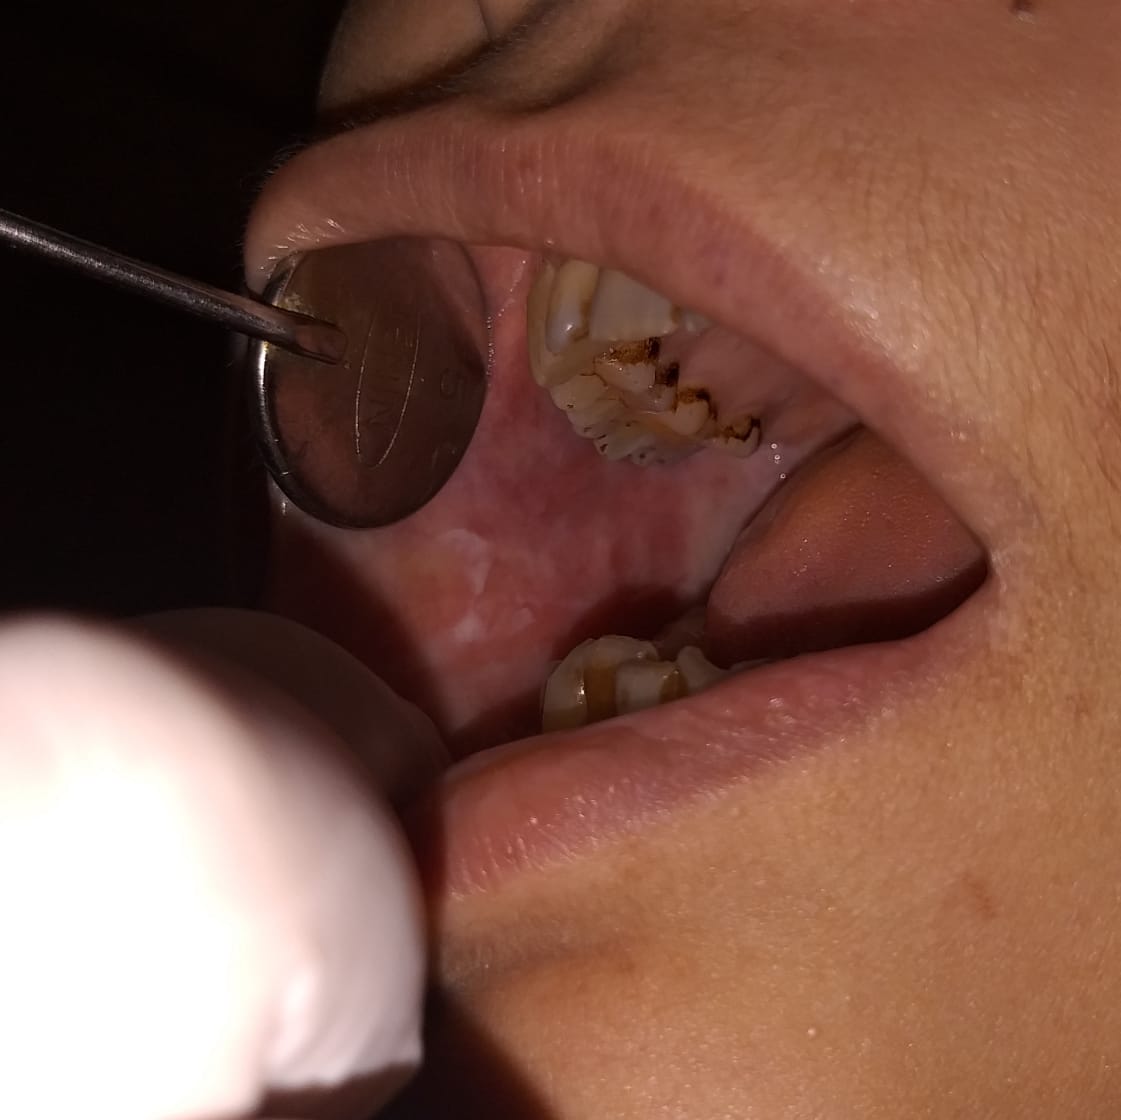

Chronic periodontitis, considered as the 6th complication of diabetes is detected early by dental check up. Other oral manifestations of diabetes can also be detected early and treated with utmost care.